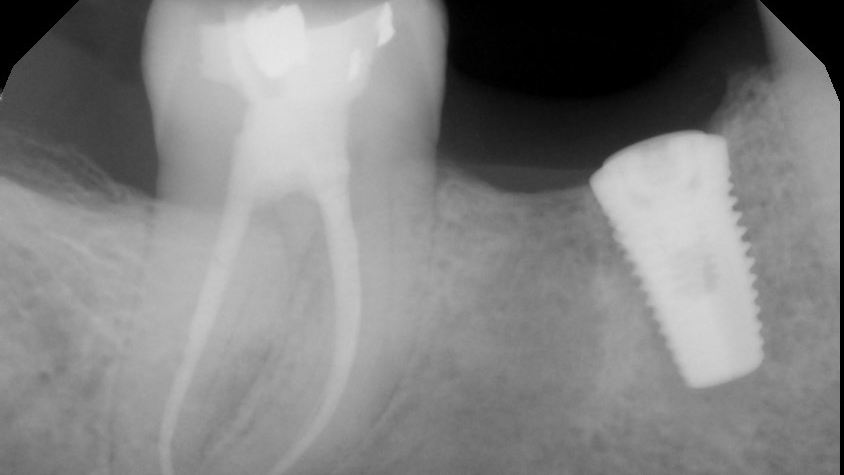

Root fracture is a common source of pain after root canal treatment and is of particular concern since it may be hard to diagnose (figure 1).5 Although new technologies such as three-dimensional imaging and microscopes have increased diagnostic ability, vertical fractures can still be hard to ascertain. Isolated periodontal pockets and a history of sharp pain that progresses to a dull throbbing pain upon mastication/palpation are common signs of fracture. Other common risk factors for fracture include: the lower second molar (most likely tooth to fracture), parafunctional habits including clenching/bruxism, large amalgam restorations, thermal injury, psychological stress, teeth with existing erosion, abrasion, and/or abfraction. A fractured tooth may need to be extracted to alleviate symptoms of pain (figure 2).

The periodontium surrounding the tooth can be a source of pain, especially if there is a concurrent periodontal lesion along with an endodontic lesion (figure 3). The tooth should be clinically examined and radiographs taken following root canal treatment to evaluate both hard and soft tissue. Hard-tissue defects, such as intrabony defects and furcation involvement, can cause inflammation leading to tooth pain. In addition, soft-tissue recession can expose root surfaces, which can then lead to sensitivity and tooth pain. Food impaction, especially if the tooth is temporized, can also mimic tooth pain. Gingival irritation from the rubber dam clamp used during the root canal can simulate tooth pain, but it is usually temporary and can be alleviated with rinses or medicaments. Referral to a periodontist may be required for pain of periodontal origin.